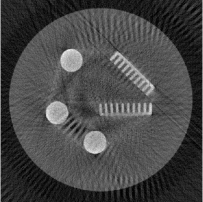

Figure 1. Phantoms for tests. (a) Head phantom used for simulation [24], (b) gel phantom used for real X-ray scan.

For the experiments, we test our method on a simulated head phantom from [24] and a real gel phantom shown in Figure 1. Here, we consider a 2D CT scenario. The detector has full coverage of the object at any projection angle, and a constant angular spacing of the rays is set in the interval of [0,π]0𝜋[0,\pi].